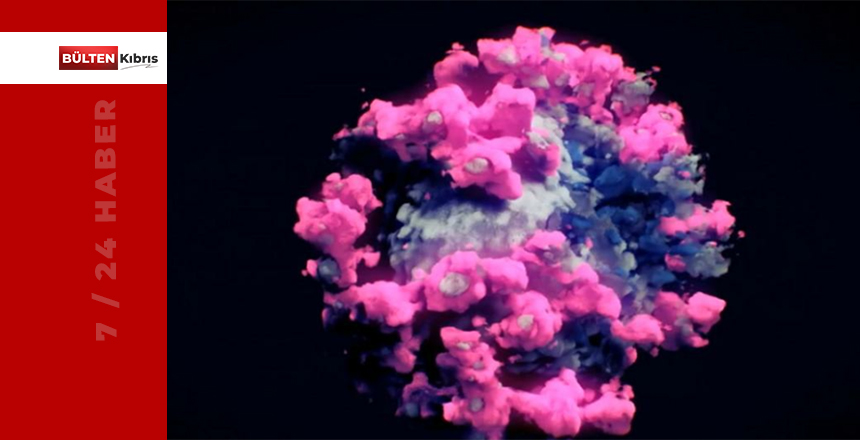

Yaklaşık 1.5 yıldır dünyanın başına bela olan corona virüsünün ilk kez fotoğrafı çekildi. Daha önceki versiyonları, hep gözlemlerin ışığı altında bilgisayarda oluşturulmuştu. Bu kez, çok farklı teknik kullanılarak, virüsün fotoğrafı çekildi ve aylarca süren çalışmayla da renklendirildi.

Yeni tür corona virüsünü (Sars Cov-2) görüntülemek için Avusturya’da Nanografik isimli bir kuruluş çalışma yaptı ve Cryo-EM Tomografi ve 3D sistemi kullanıldı.

Ardından Viyana Teknik Üniversitesi’nde aylarca süren çalışma sonucunda, virüsün bir bölümü kirli mavi, bir bölümü pembe çıkıntılı yüzeyleriyle tüm gerçek şekli ortaya çıkarıldı. Yeni teknoloji ile fotoğraflanan, tüm ayrıntılarıyla ortaya çıkarılan virüs artık biyolojik mikroskoplarla daha detaylı olarak incelenebilecek.